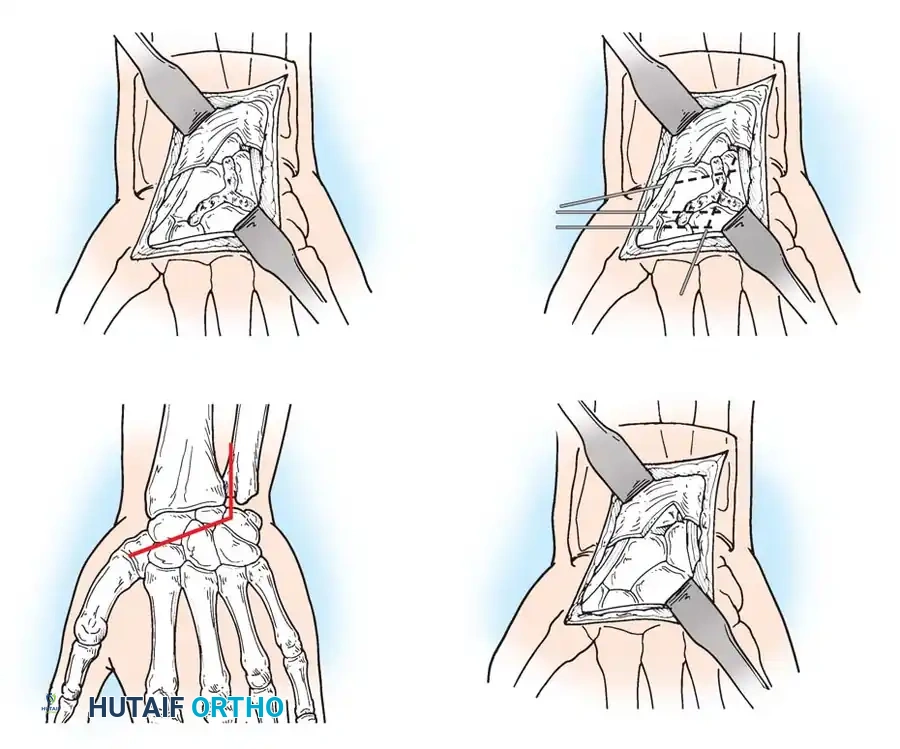

Surgical Management of Scapholunate Dissociation

Acute Injuries (<4 weeks):

Closed reduction with percutaneous pinning (placing 0.045-inch K-wires from the scaphoid to the capitate and lunate) can be attempted. However, open reduction through a dorsal approach is generally preferred. This allows direct closure of the scapholunate gap, K-wire fixation, and primary repair of the dorsal SL interosseous ligament using suture anchors.